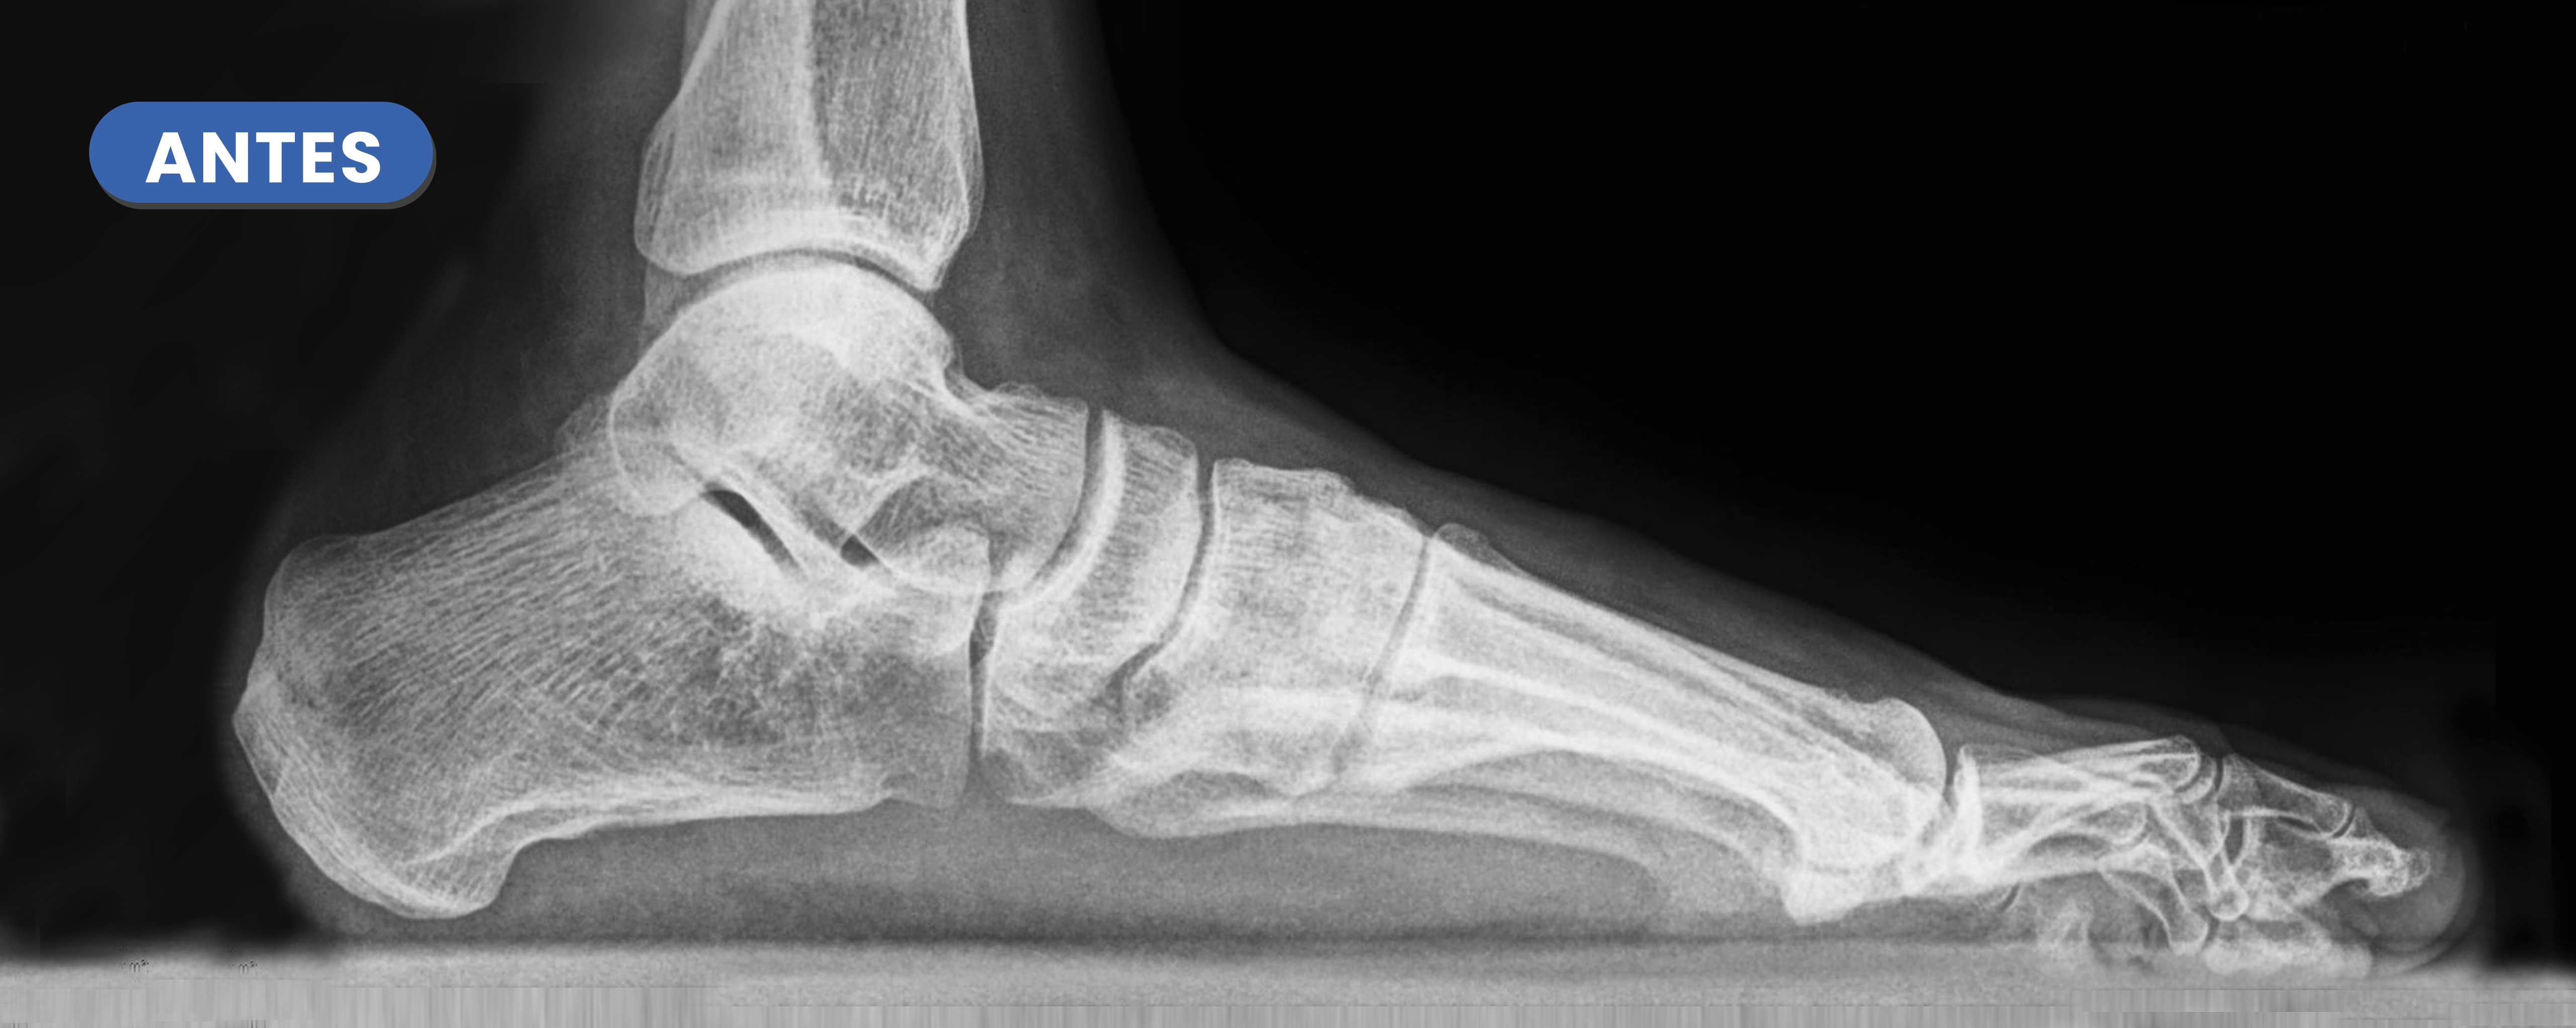

Te mostramos casos reales resueltos mediante cirugía de mínima incisión por el Dr. Rubén Lorca y su equipo.

Mueve las flechas para visualizar el antes y después.

En estas radiografías se puede observa el aumento de tamaño del arco interno (ALI ) tras la realización de la osteotomía varizante fijada mediante un tornillo.